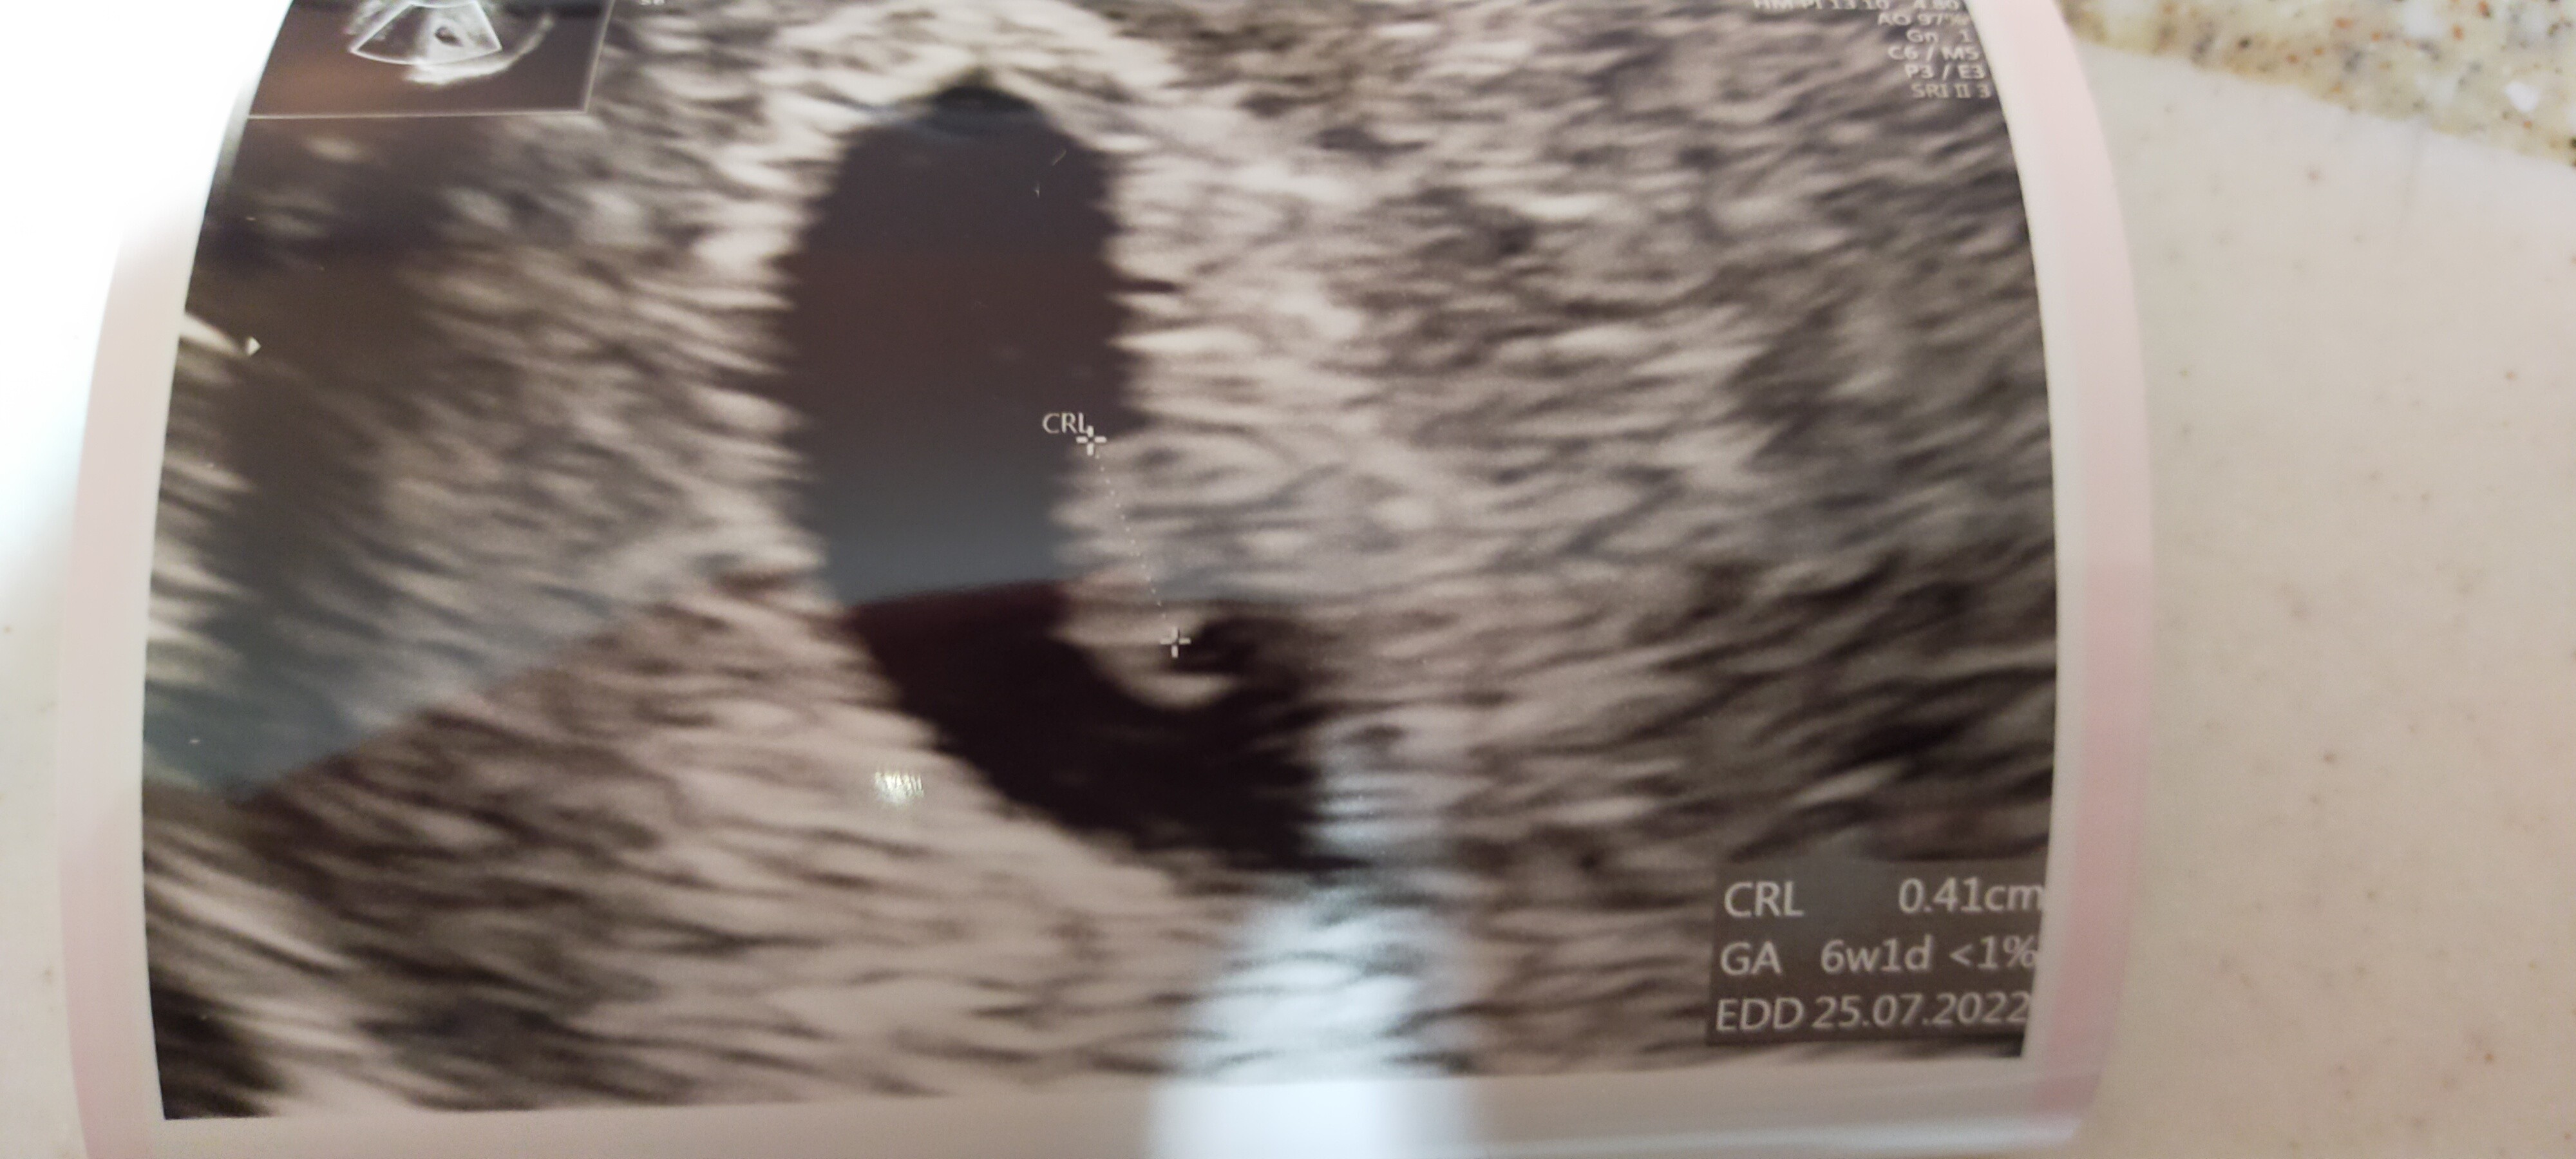

teraz sytuacja co najmniej dziwna... dziś byłam na kolejnej wizycie z której wynika ze to 6t5d więc strasznie mało ta ciąża urosła

dodam, że nadal jest tylko puste jajo bez zarodka

chociaż z usg termin wychodzi na 14 lipca... moja Pani dr zaleciła zrobić mi bęte jutro i w piątek i dać jej znać o wyniku, żeby zobaczyć co dalej.... jakoś nie umiem być dobrej myśli